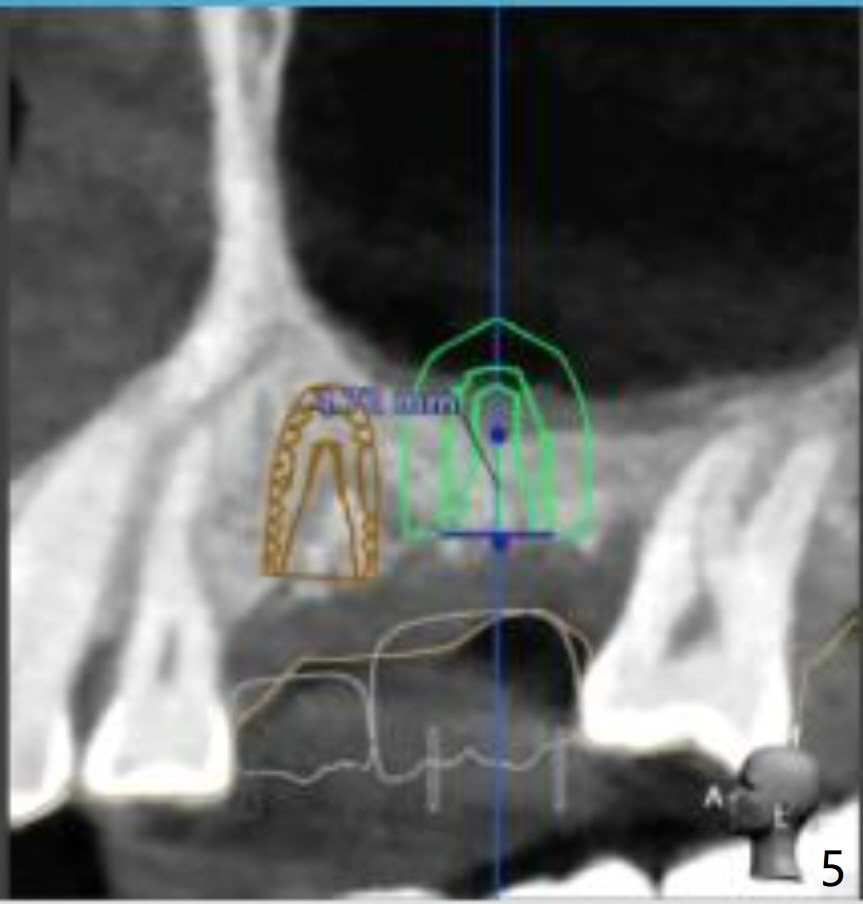

Short Implants with Sinus Lift at #14

Return to Upper Molar Immediate Implant, Armaments

Xin Wei, DDS, PhD, MS 1st edition 08/14/2018, last revision 08/30/2018